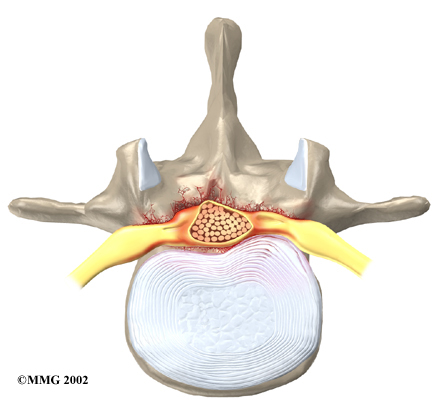

Degeneration: Degeneration is the most common cause of spinal stenosis. Wear and tear on the spine from aging and from repeated stresses and strains can cause many problems in the lumbar spine. The intervertebral disc can begin to collapse, and the space between each vertebrae shrinks. Bone spurs may form that stick into the spinal canal and reduce the space available to the spinal nerves. The ligaments that hold the vertebrae together may thicken and also push into the spinal canal. All of these conditions cause the spinal canal to narrow.

Disc herniation: Spinal stenosis can occur when an intervertebral disc in the low back herniates (ruptures). Normally, the shock-absorbing disc is able to handle the downward pressure of gravity and the strain from daily activities. However, if the pressure on the disc is too strong, such as landing from a fall in a sitting position, the nucleus inside the disc may rupture through the outer annulus and squeeze out of the disc. This is called a disc herniation. If an intervertebral disc herniates straight backward, it can press against the nerves in the spinal canal, causing symptoms of spinal stenosis.

The lamina is the covering layer of the bony ring of the spinal column. It forms a roof-like structure over the back of the spinal canal. When the nerves in the spinal canal are being squeezed by a herniated disc or bone spurs, a lumbar laminectomy removes the entire lamina to release pressure on the spinal nerves. This is the primary type of surgery used for lumbar spinal stenosis.